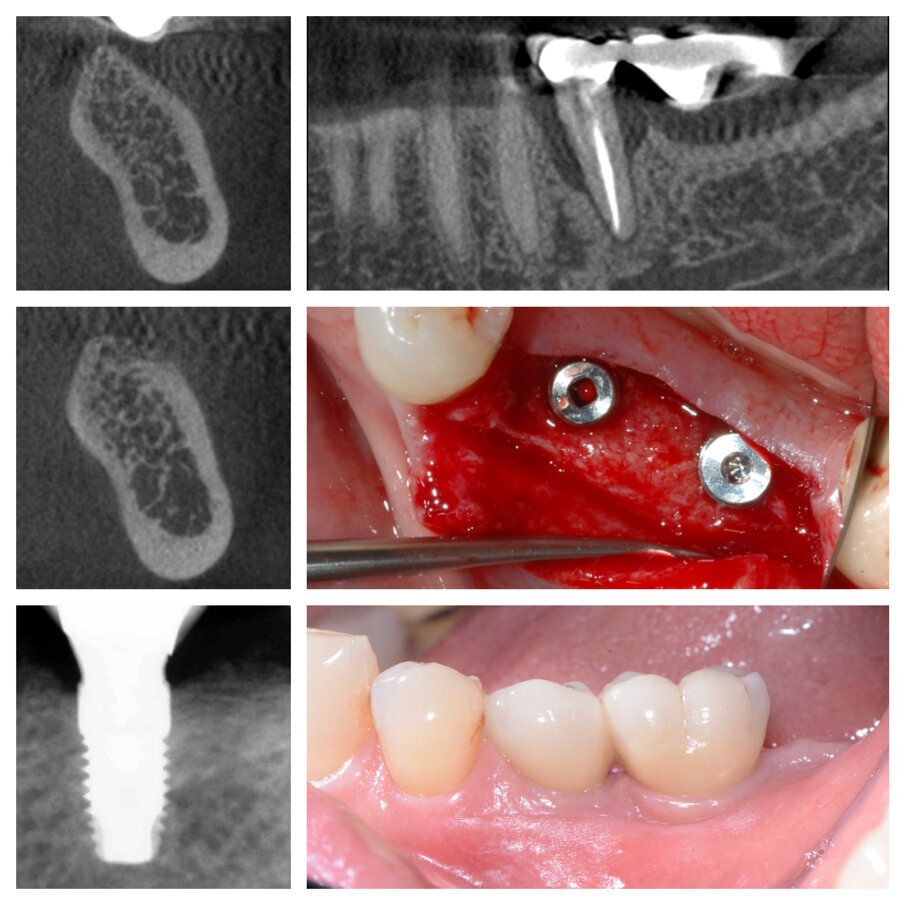

Fig. 1a_Estrazione di radice distale di 46 e innesto su deficit di 45 e 46.

Fig. 1b_Cambiamento dei tessuti a 22 giorni.

Fig. 1c_Aumento orizzontale dei tessuti duri del 50%.

Fig. 1d_Tessuti duri prima e dopo la tecnica S.A.T., posizionamento implantare.

Fig. 1e_Condizionamento tessuti molli e protesi definitiva.